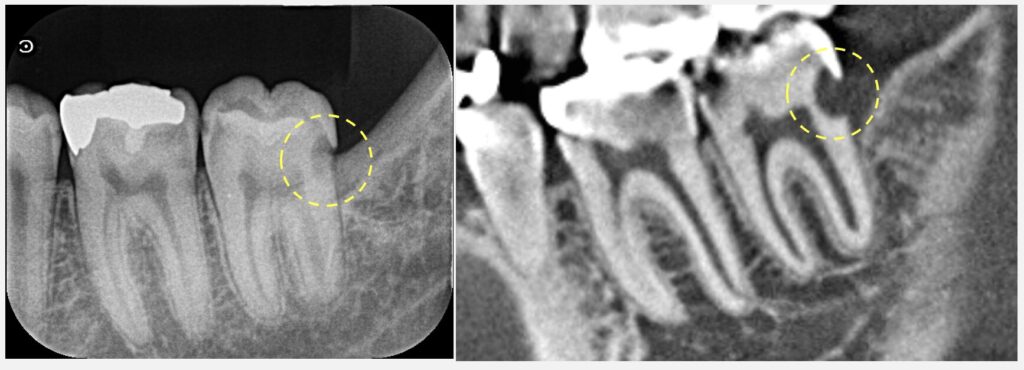

ただし、虫歯の位置が非常に深いのが問題です。歯の神経を残す処置というのは、ラバーダムで防湿を行い、かつ非常に細かな器具操作が必要となります。今の状態は歯茎からさらに深部に虫歯が進んでおり、処置のアクセスの困難さなどから、おそらく十分な歯髄保存治療を行うことは難しいと考えられます。

冷たいものでしみる奥歯の歯の神経を残したい【30代男性】歯髄保存療法は不可能と診断し根管治療を行った下顎大臼歯_症例50